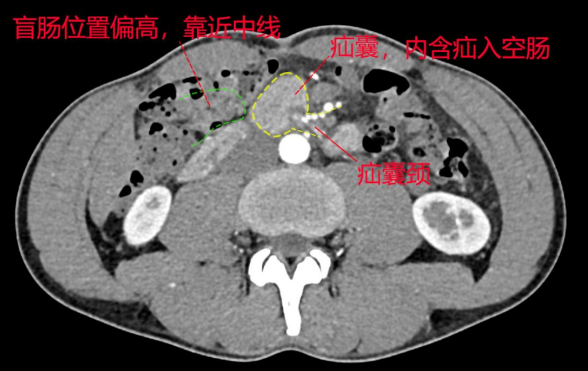

▲CT增强扫描可见,患者空肠经肠系膜上动脉与腹主动脉之间疝入右上腹部,由于已进行胃肠减压,故肠管积液、扩张征象消失;患者盲肠高位。

术中,陈志辉及其团队经过探查发现患者腹腔广泛粘连形成,大网膜与前腹壁、小肠也存在多处粘连,盲肠被牵拉到右中腹部,小肠经十二指肠旁的隐窝疝至右侧腹腔。